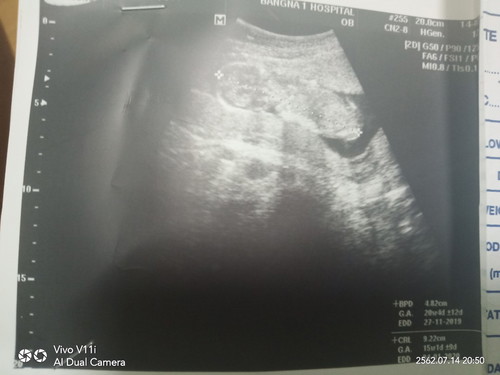

แม่ๆคนไหนลูกดิ้นแล้วบ้างคะ

15สัปดาห์แล้วจร้า